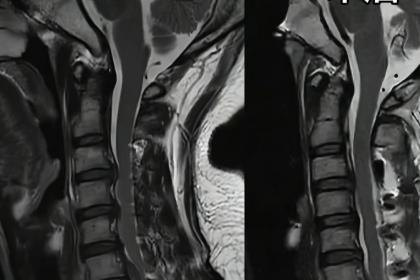

随着年龄增长,不少老年人会受到颈腰椎问题困扰,严重的脊髓压迫可能导致疼痛、麻木甚至行走困难。很多家属和患者会问:老年人能做解除脊髓压迫的手术吗?

随着医疗技术进步,年龄本身已不再是手术的禁区。许多高龄患者通过微创或常规手术,成功解除了压迫,显著提升了生活质量。医生会综合评估患者的脊髓受压程度、症状轻重以及整体身体状况。